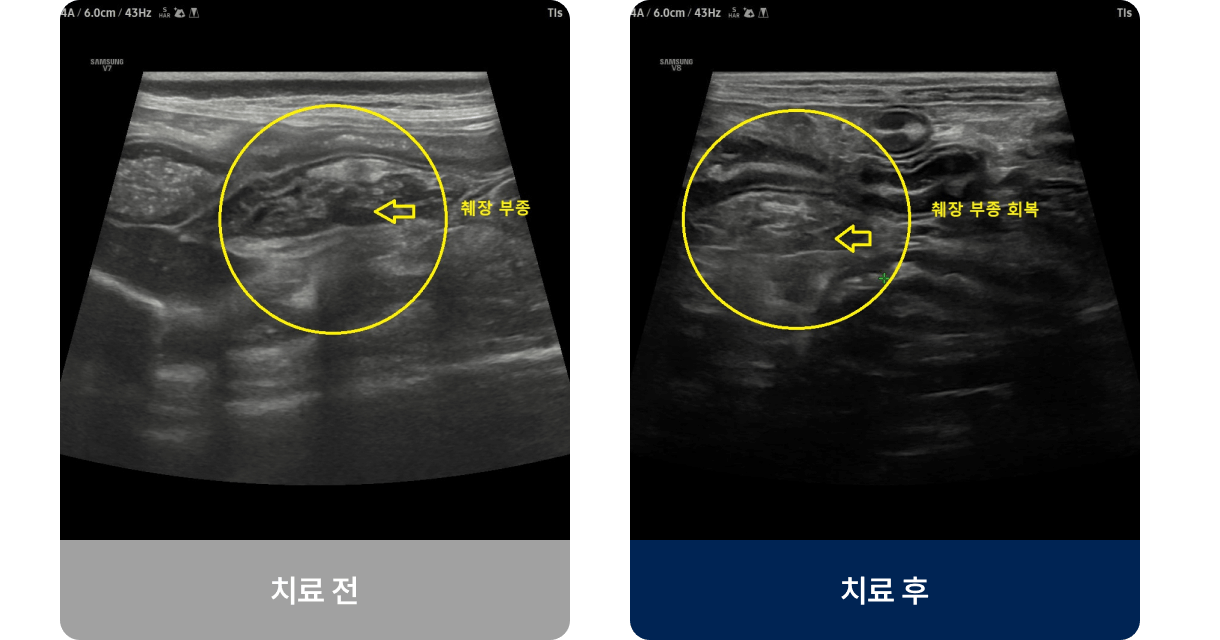

고지방 식이, 과식, 스트레스, 특정 약물 등이 원인이 되어 췌장에 염증이 생기는 질환입니다. 주로 중·노령견이나 비만한 아이에게 많이 발생하며, 밥을 먹은 뒤 구토하거나 복통으로 웅크리는 증상을 보입니다. 진행되면 식욕 저하, 체중 감소, 무기력, 탈수로 이어질 수 있습니다.